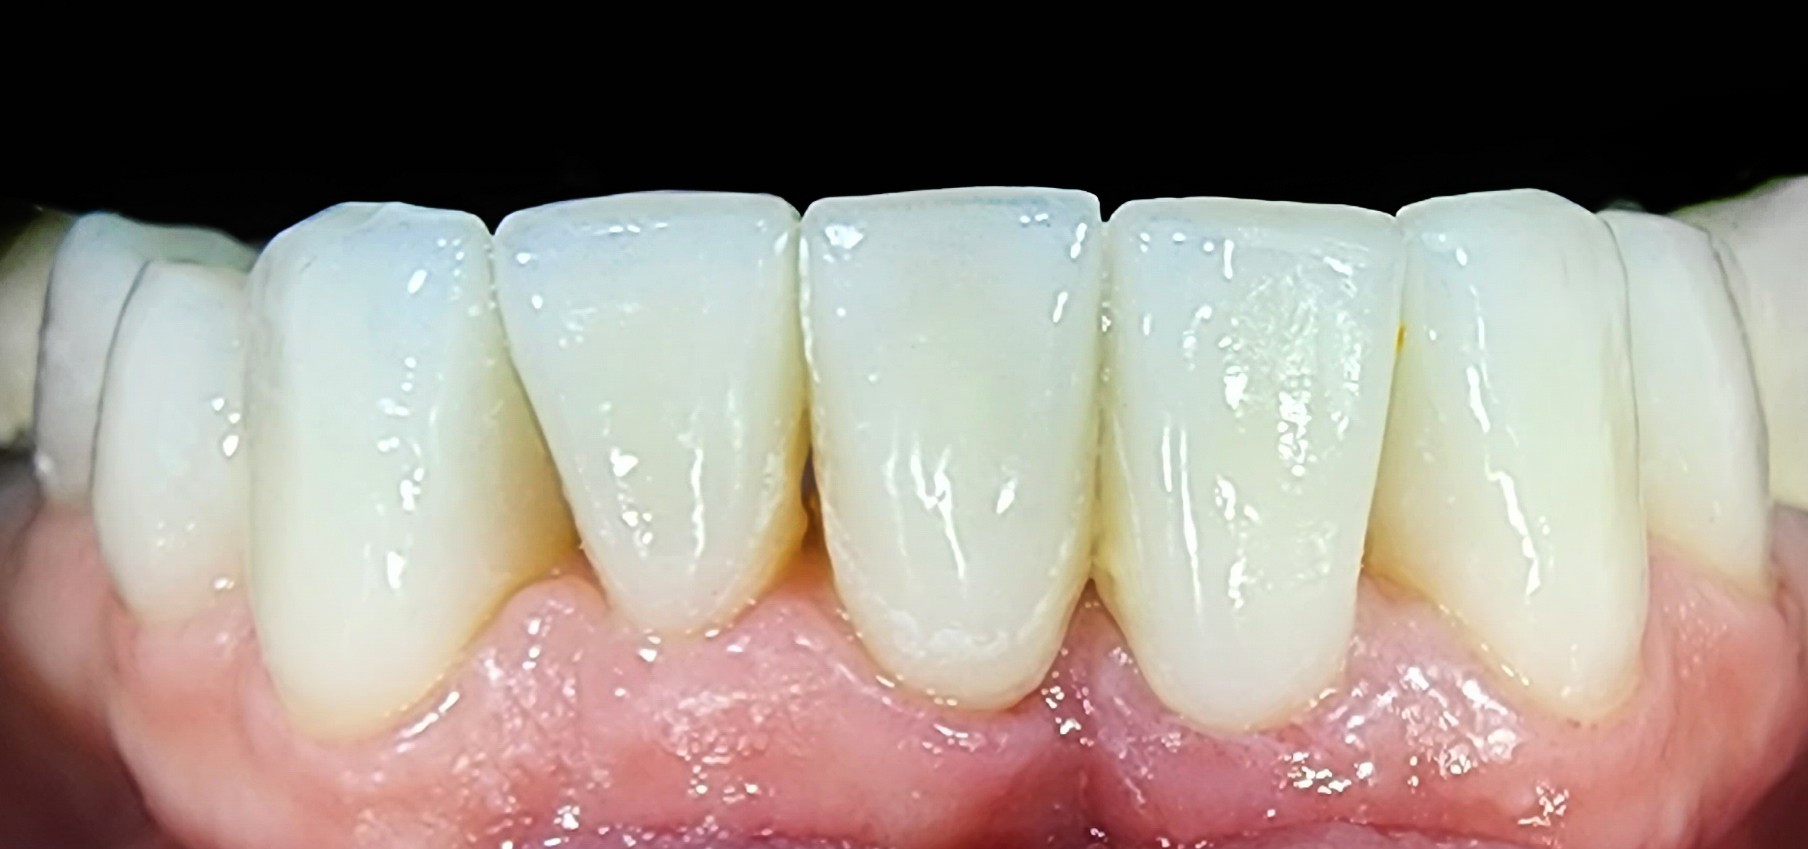

גלריה ציפוי חרסינה לשיניים

כתמים על השיניים